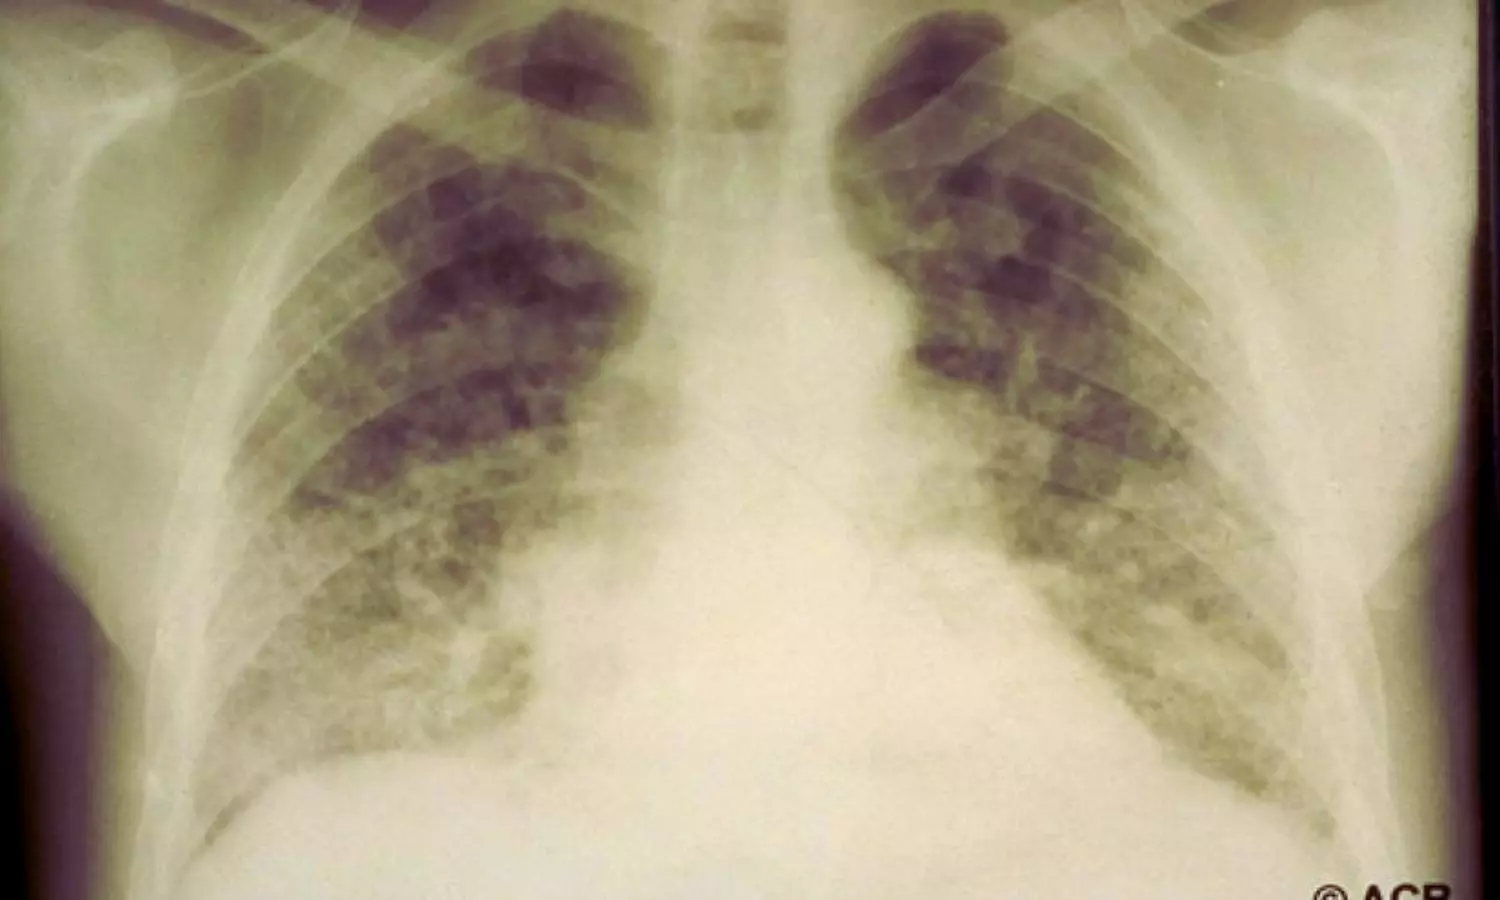

Interstitial Lung Disease Significantly Increases Risk of All Lung Cancer Types: Study

Emphysema at CT lung screening increases death risk in asymptomatic adults: Study